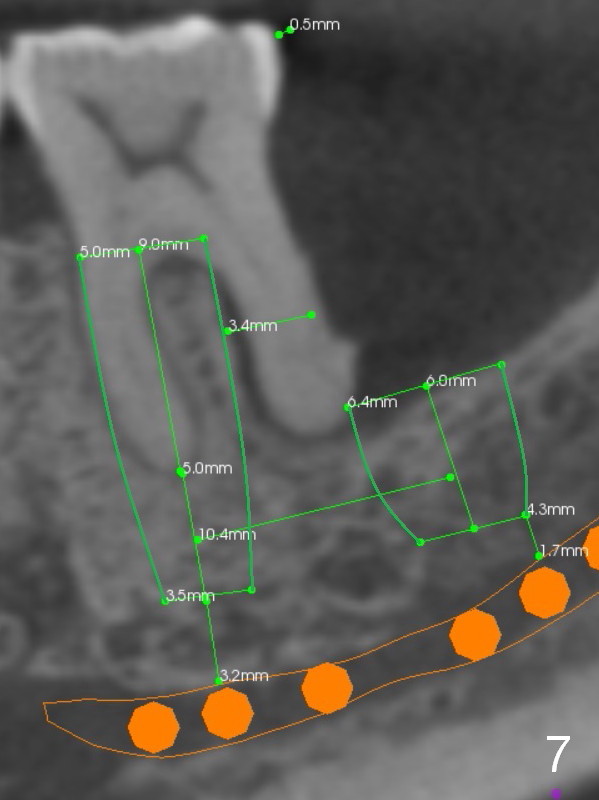

There is severe bone resorption around the distal root of the lower left 1st molar of the 56-year-old man (WG), while the loss of the 2nd molar is associated with limited bone height (Fig.1). A 5x14 mm implant will be placed at the mesial socket of #19 and 5.9 or 6.4x6 mm one is at the mesial site of #18 (Fig.7-9). Use a 2 mm pilot drill with 6 mm stopper from Sinus Master Kit (with extension) to initiate osteotomy at #18 immediately distal to the crown of #19, parallel to the long axis of the latter (Fig.2). After inserting a parallel pin at #18, extract the tooth #19 (Fig.3, antibiotic pending) and start osteotomy with a 2 mm pilot drill with 14 mm stopper (Fig.4). Insert the calibrated parallel pin at #19 (Fig.5) and measure the distance between the two parallel pins (approximately 10 mm, Fig.7). Sequential osteotomy and application of the Tatum taps (Fig.6 red rectangle) will push the septum distal (green arrow). As to #18 osteotomy, trephine, final and tap drills are to be used with control of the depth: 6 mm (Fig.7,9).